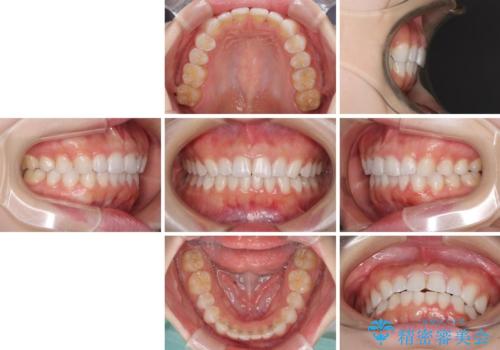

デコボコと深い咬み合わせの改善 インビザラインによる矯正治療

- 口元のデコボコと深い咬み合わせ(ディープバイト)を気にして来院された患者様です。

インビザラインによる上下歯列の拡大と、IPR(歯と歯の間を削る)にるスペースの獲得により、口元のデコボコとディープバイトを改善することとしました。

インビザラインは、装着していない時間がどれだけ短いかが、治療期間を大きく左右します。こちらの患者様は1日22時間以上、毎日欠かさず装着してくださったため、1年強という短期間で満足のいく歯列に整えることができました。